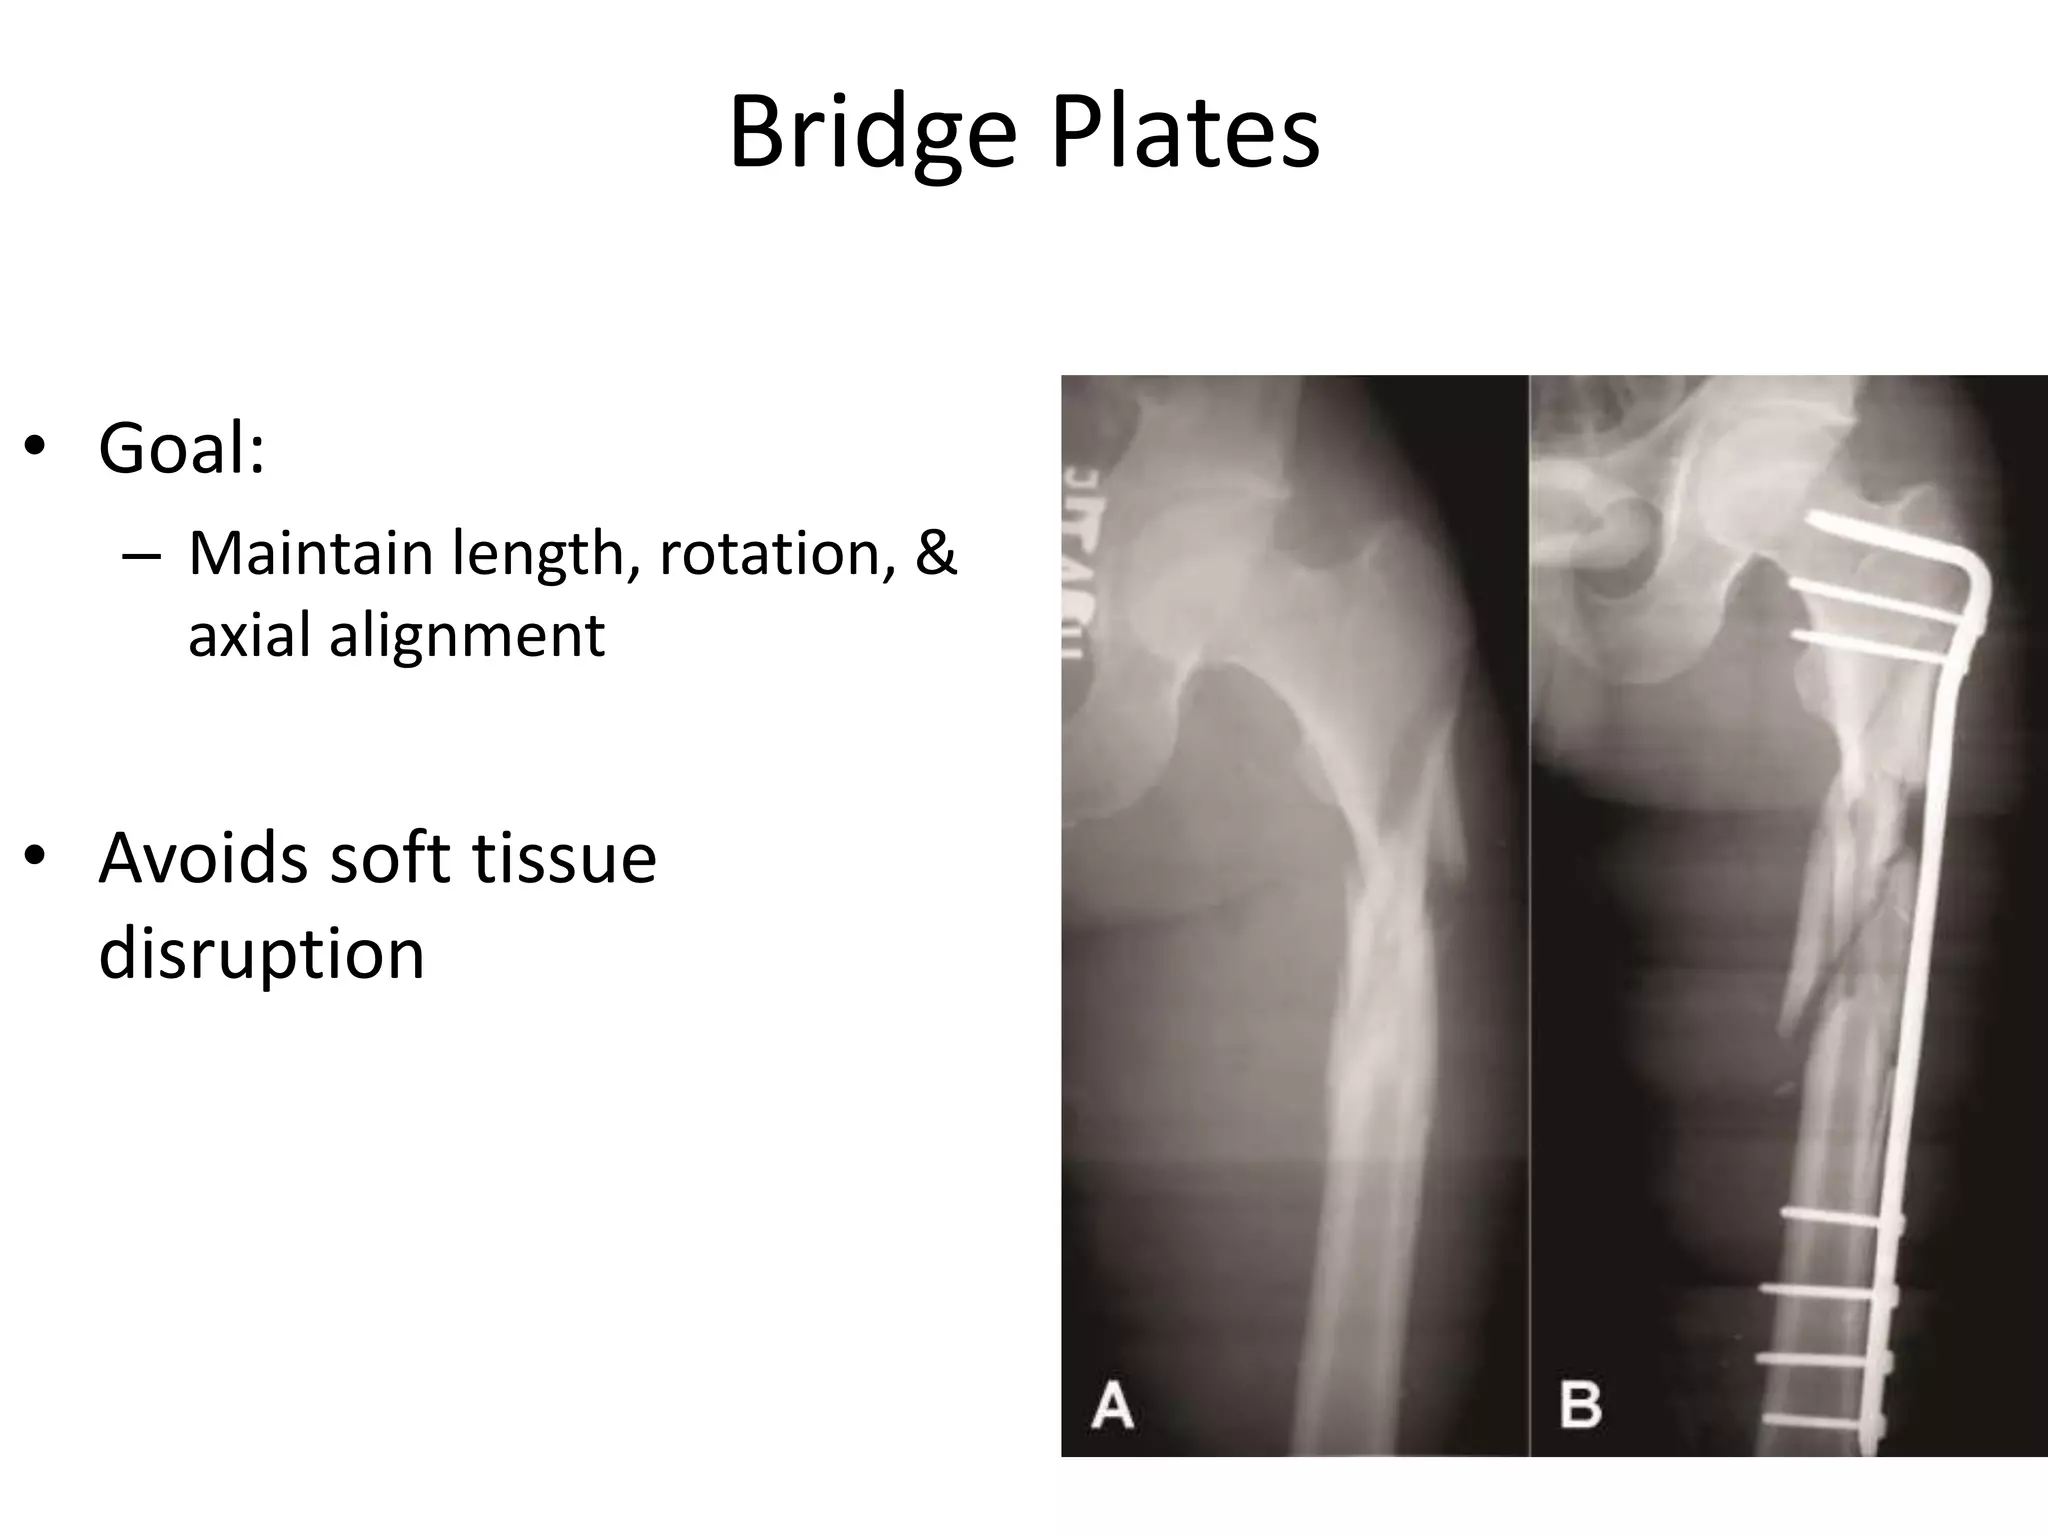

Bridge Plates

• Goal:

– Maintain length, rotation, &

axial alignment

• Avoids soft tissue

disruption

Bridge Plates • Goal: –Maintain length, rotation, & axial alignment • Avoids soft tissue disruption